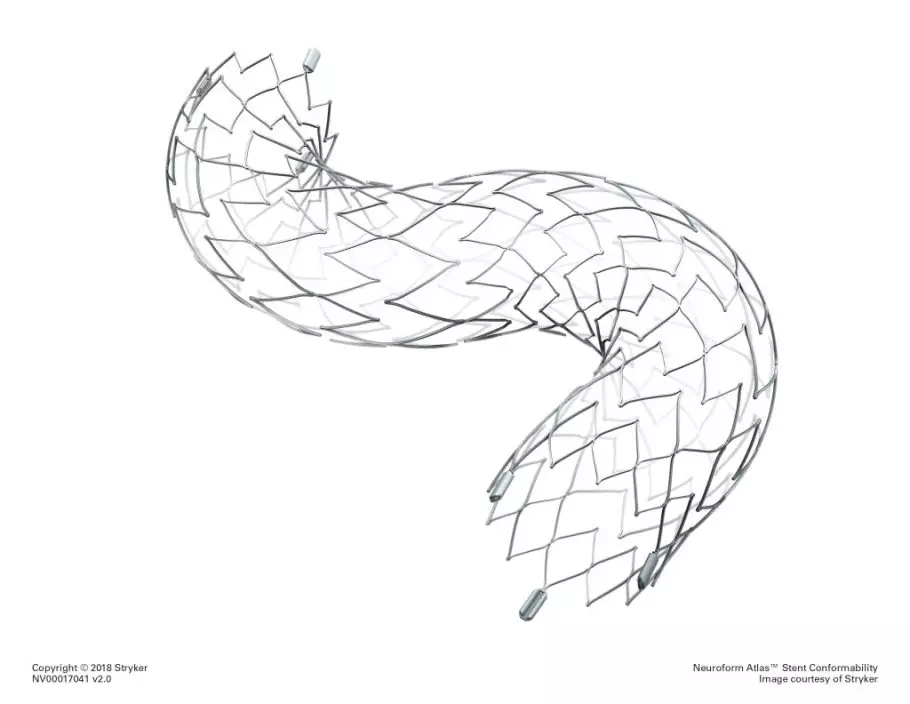

Neuroform Atlas 血管支架。 stryker官網

而底動脈是人腦血管中重要的主幹血管,供應腦幹、小腦及部分大腦組織,周圍遍布穿支血管,對術者的操作要求極高。手術過程中,手術者需要操作導絲及導管,通過迂曲的血管定位至狹窄的病灶,通過球囊擴張血管後精準釋放支架。